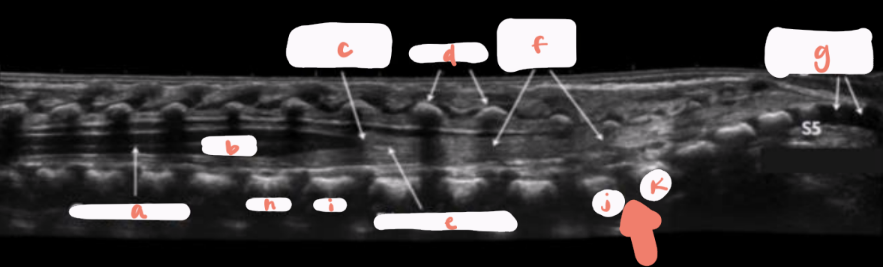

a

L1

b

L2

c

L3

d

L4

e

L5

f

LSJ

g

S1

h

S2

i

S3

J

S4

k

S5

central canal of spinal cord

hypoechoic spinal cord

conus medullaris

pedicles/vertebral arches

nerve roots

coccygeal segments

T12

filum terminale

arrow